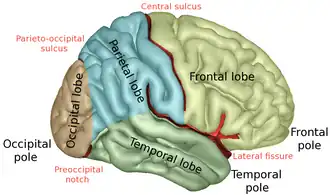

| Lobes of the cerebral cortex (right hemisphere view) | |

Lateral surface. Four lobes visible. | |

The lobes of the brain are the four major identifiable regions of the human cerebral cortex, and they comprise the surface of each hemisphere of the cerebrum.[1] The two hemispheres are roughly symmetrical in structure, and are connected by the corpus callosum. Some sources include the insula and limbic lobe but the limbic lobe incorporates parts of the other lobes. The lobes are large areas that are anatomically distinguishable, and are also functionally distinct. Each lobe of the brain has numerous ridges, or gyri, and furrows, sulci that constitute further subzones of the cortex.[2] The expression "lobes of the brain" usually refers only to those of the cerebrum, not to the distinct areas of the cerebellum.

Frontal lobe

The frontal lobe is located at the front of each cerebral hemisphere and positioned in front of the parietal lobe and above and in front of the temporal lobe. It is separated from the parietal lobe by a space between tissues called the central sulcus, and from the temporal lobe by a deep fold called the lateral sulcus, also called the Sylvian fissure. The precentral gyrus, which forms the posterior border of the frontal lobe, contains the primary motor cortex (area 4 under the Brodmann area architecture) which controls voluntary movements of specific body parts. The precentral region also contains the premotor cortex (Brodmann area 6).

Parietal lobe

The parietal lobe is positioned above the occipital lobe and behind the frontal lobe and central sulcus.

Occipital lobe

Temporal lobe

The temporal lobe is located beneath the lateral fissure on both cerebral hemispheres of the mammalian brain.[9]

Lateral view of left hemisphere.

Lateral view of left hemisphere. -